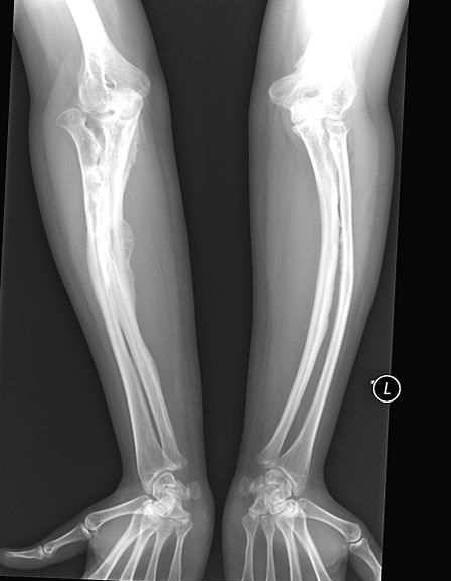

Žena povećane krhkosti kostiju uspjela je sretno izaći ženi se. Anastasija Marukova, kojoj je dijagnosticirano dijete “nesavršena osteogeneza” preživela je mnoge probleme. Ona je slomio kosti 40 puta. Otac nije mogao podnijeti život s teško bolesnim kćerke i rano ih ostavio kod majke. Ali tada je Anastasia imala sreće muž – voljena osoba prati je svuda, jer bezbrižno pokret joj obećava novu prekretnicu.